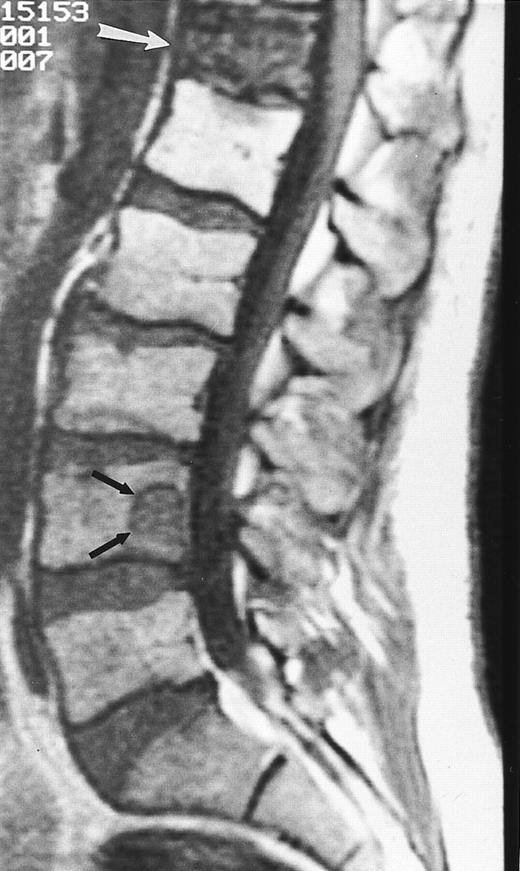

An 8-year-old boy with Burkitt's lymphoma and diffuse marrow involvement. Fat-suppressed, T2-weighted fast spin echo (3000/96, TR/TE) sagittal MR image of the lumbar spine shows heterogeneous signal intensity of the bone marrow and epidural extension of tumor (arrowheads) at the level of L5 and L2, with apparent preservation of the vertebral cortex.